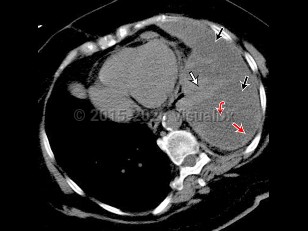

Clinically, effusions may be categorized as either transudates or exudates. Thoracentesis and laboratory evaluation as well as radiographic characteristics distinguish between these types.

History and imaging findings may support one etiology of pleural effusion over another, but analysis of the pleural fluid provides more definitive diagnosis as well as therapeutic management in cases where the pleural effusion is impeding respiratory status.

Transudative pleural effusions are due to conditions in which there is an imbalance in hydrostatic and oncotic forces such as with heart failure, cirrhosis, or nephrotic syndrome.

Exudative effusions are due to inflammation from infection or noninfectious etiologies, injury, malignancy, and impaired lymphatic drainage. The primary method of distinguishing transudate from exudate is Light's criteria: